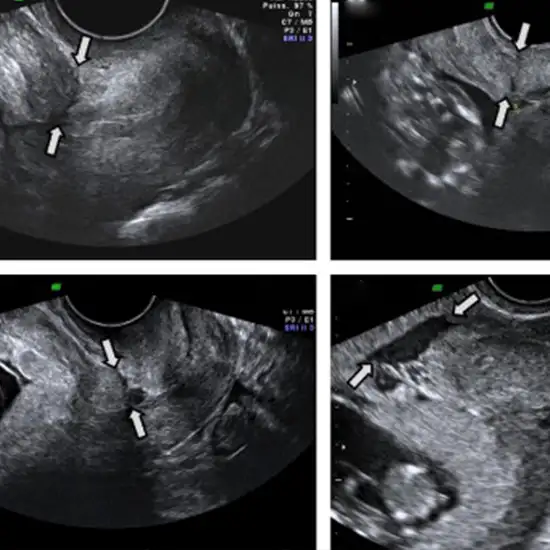

Ultrasound whole abdomen with TVS (Trans Veginal Scan) is the diagnostic procedure, which uses sound waves for the detection of abnormality in the vegina and the fetus. A whole abdomen ultrasound is used to check for abnormalities in the abdomen and the organs like the liver, kidney, stomach etc. present in the abdomen. Transvaginal ultrasound (TVS) also known as endovaginal ultrasound is used to check for the reproductive health of females. This involves the insertion of a transducer or probe into the vegina.

Transvaginal ultrasound is used to detect an abdominal pelvic ultrasound, unexplained vaginal bleeding, pelvic pain, ectopic pregnancy, infertility, and fibroids and verify whether the IUD is placed properly or not.

The ultrasound technician will apply a clear gel to the upper abdomen and then move an ultrasonic probe over your abdominal skin to perform an ultrasound of that area. Sound waves are emitted by the ultrasonic probe (transducer) and reflect off the organs and surrounding structures in the upper abdomen. The ultrasonic device then transforms the reflected sound waves into pictures. Before the scan Patient is asked to lie on a diagnostic table and bend the knees. After covering the ultrasound probe with lubricating gel and a condom, your doctor will insert it into the vagina. If the patient has allergies towards latex, she can alert the healthcare provider. The procedure gives the reproductive health and condition of the fetus.

Transvaginal Ultrasound is a test used to detect the female uterus, placenta, ovaries, tubes, cervix and pelvic area.